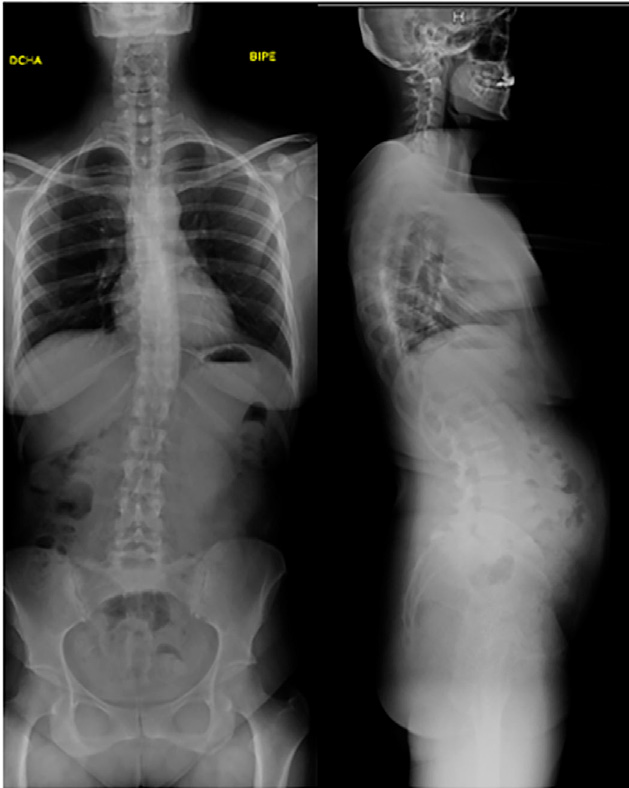

- RMN de columna lumbar: espondilolisis bilateral L5 con espondilolistesis grado II sobre S1. La listesis condiciona discreta estenosis de canal a nivel sacro.

- Radiografías simples columna lumbosacra: espondilolistesis L5-S1 grado II-III.